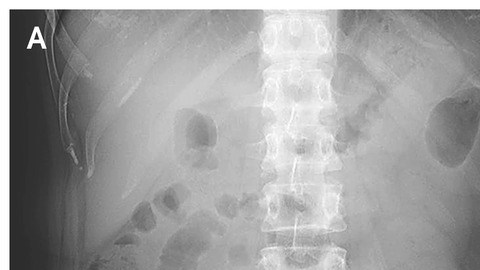

Una mujer muestra hinchazón por tres años y el motivo son dos gasas que quedaron en su interior. Crédito: New England Journal of Medicine

Los médicos decidieron hacerle una tomografía computarizada y el escaneo reveló la sorprendente verdad.

Descubrieron dos “estructuras fibrosas e hiperdensas” cerca de cada una de sus caderas, según mostraba el informe médico. Identificaron los artículos como esponjas de gasa después de dividir cada uno de ellas por la mitad.